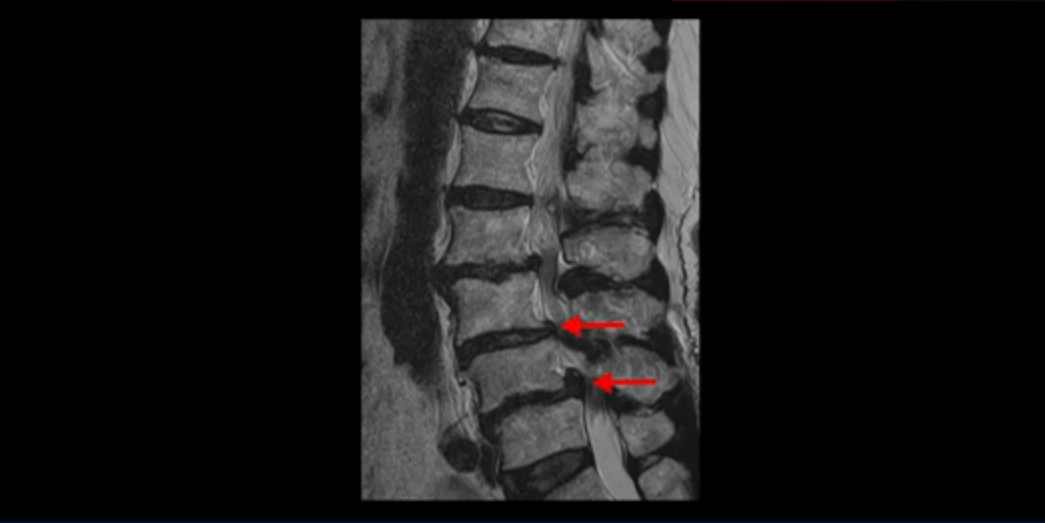

보시다시피 허리 다섯 마디 전부가 다 퇴행되어 있고,

두 마디에 전방전위증이 있고,

2번 3번,

3번 4번,

4번 5번에 중심성 협착이 심하고

거의 모든 추간공 즉, 신경가지가 좌우로 빠져나가는 구멍이 다 좁아져 있습니다.

척추가 이런 상태니까 양쪽 엉치와 다리가 다 저리고 아프며 지팡이를 짚고 겨우 걷는 상태였습니다. 이렇게 국내 최상위 대학병원에서도 수술하지 말라고, 수술하면 더 안 좋을 거라는 얘기를 들은 고령의 말기 협착증 환자가 근육 재활치료로 좋아질 수 있을까요? 당연히 좋아질 수 있습니다. 무슨 근거로 이렇게 자신있게 얘기하는 걸까요? 왜냐하면 근육이 좋아지는 만큼 협착증 증상이 좋아지기 때문입니다. 근육은 뭉친 걸 반복해서 풀어주고 환자 상태에 맞는 적절한 운동을 잘 하는만큼 좋아질 가능성이 매우 높습니다. 저희는 수많은 치료 후기와 임상시험을 통한 국제학술 논문 등을 통하여 이렇게 여러 마디가 안 좋은 고령의 말기 협착증 환자분들도 근육을 치료하여 근육 상태가 좋아지면 협착증 증상이 좋아진다는 걸 계속해서 보여드리고 있습니다.